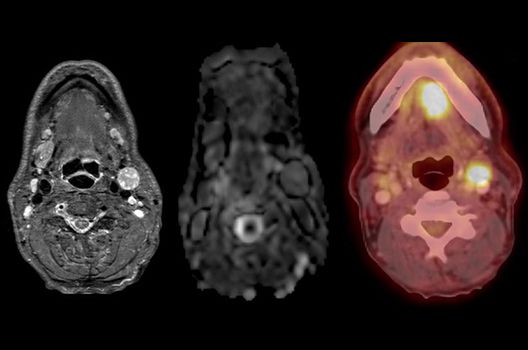

- PET/MRT in der Neuroonkologie

- Molekulare Bildgebung mit innovativen Tracern in Kooperation mit der Nuklearmedizin und Radiopharmazie

Die Hybridbildgebung mittels PET/MRT spielt insbesondere in der onkologischen Bildgebung eine wichtige Rolle. Eine mögliche Fragestellung ist die Unterscheidung zwischen einem Tumorrezidiv oder therapeutisch assoziierten Veränderungen insbesondere dann, wenn diese Frage mittels MRT alleine nicht beantwortet werden kann.

Die bildgebende Diagnostik und Verlaufsbeurteilung von Tumoren des Nervensystems ist einer der klinischen und Forschungsschwerpunkte unserer Abteilung. Eine besondere Bedeutung kommt der Hybrid-Bildgebung zu. Das Universitätsklinikum verfügt über einen integrierten Ganzkörper-PET/MRT-Scanner, der die Vorteile der MRT-Bildgebung und der Positronenemissionstherapie (PET) vereinigt. Aufgrund der langjährigen klinischen Arbeit und Forschungstätigkeit mit diesem Gerät hat die Neuroradiologie Tübingen maßgeblich zur Etablierung dieses Verfahrens beigetragen. Auch weiterhin forschen wir intensiv an neuen Methoden zur frühen Einordnung von Tumoren und insbesondere Tumorrezidiven, die mit anderen Methoden häufig nicht erfasst werden können.